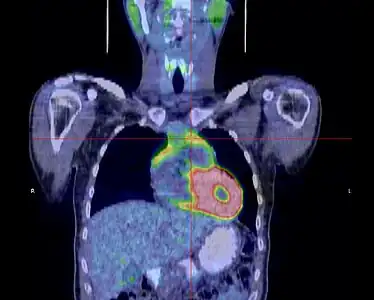

- Thymome de type B1 en TEP scanner

Coupe transversale. Les trois clichés sont extraits du même examen.

Coupe frontale ; la tumeur est à l'intersection des lignes rouges.